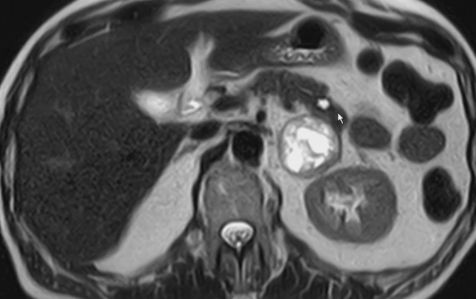

![]() MR, T2-Bild | |

| zurück Home | Phaeochromozytom | Phäochromozytom der linken Nebenniere

| Klinik | Tumor des Nebennierenmarks. Sezernieren Katecholamine. | ||

| Lokalisation | 98% im Abdomen. 10% doppelseitig. | ||

| extraadrenal | 10% der Phaeochromozytome sind extraadrenal und heißen Paragangliome. | Es ist wichtig, festzustellen, ob der Tumor in der Nebenniere oder daneben liegt. Intraadrenale Tumoren sind immer benigne, paraadrenale zu 20% maligne. | |